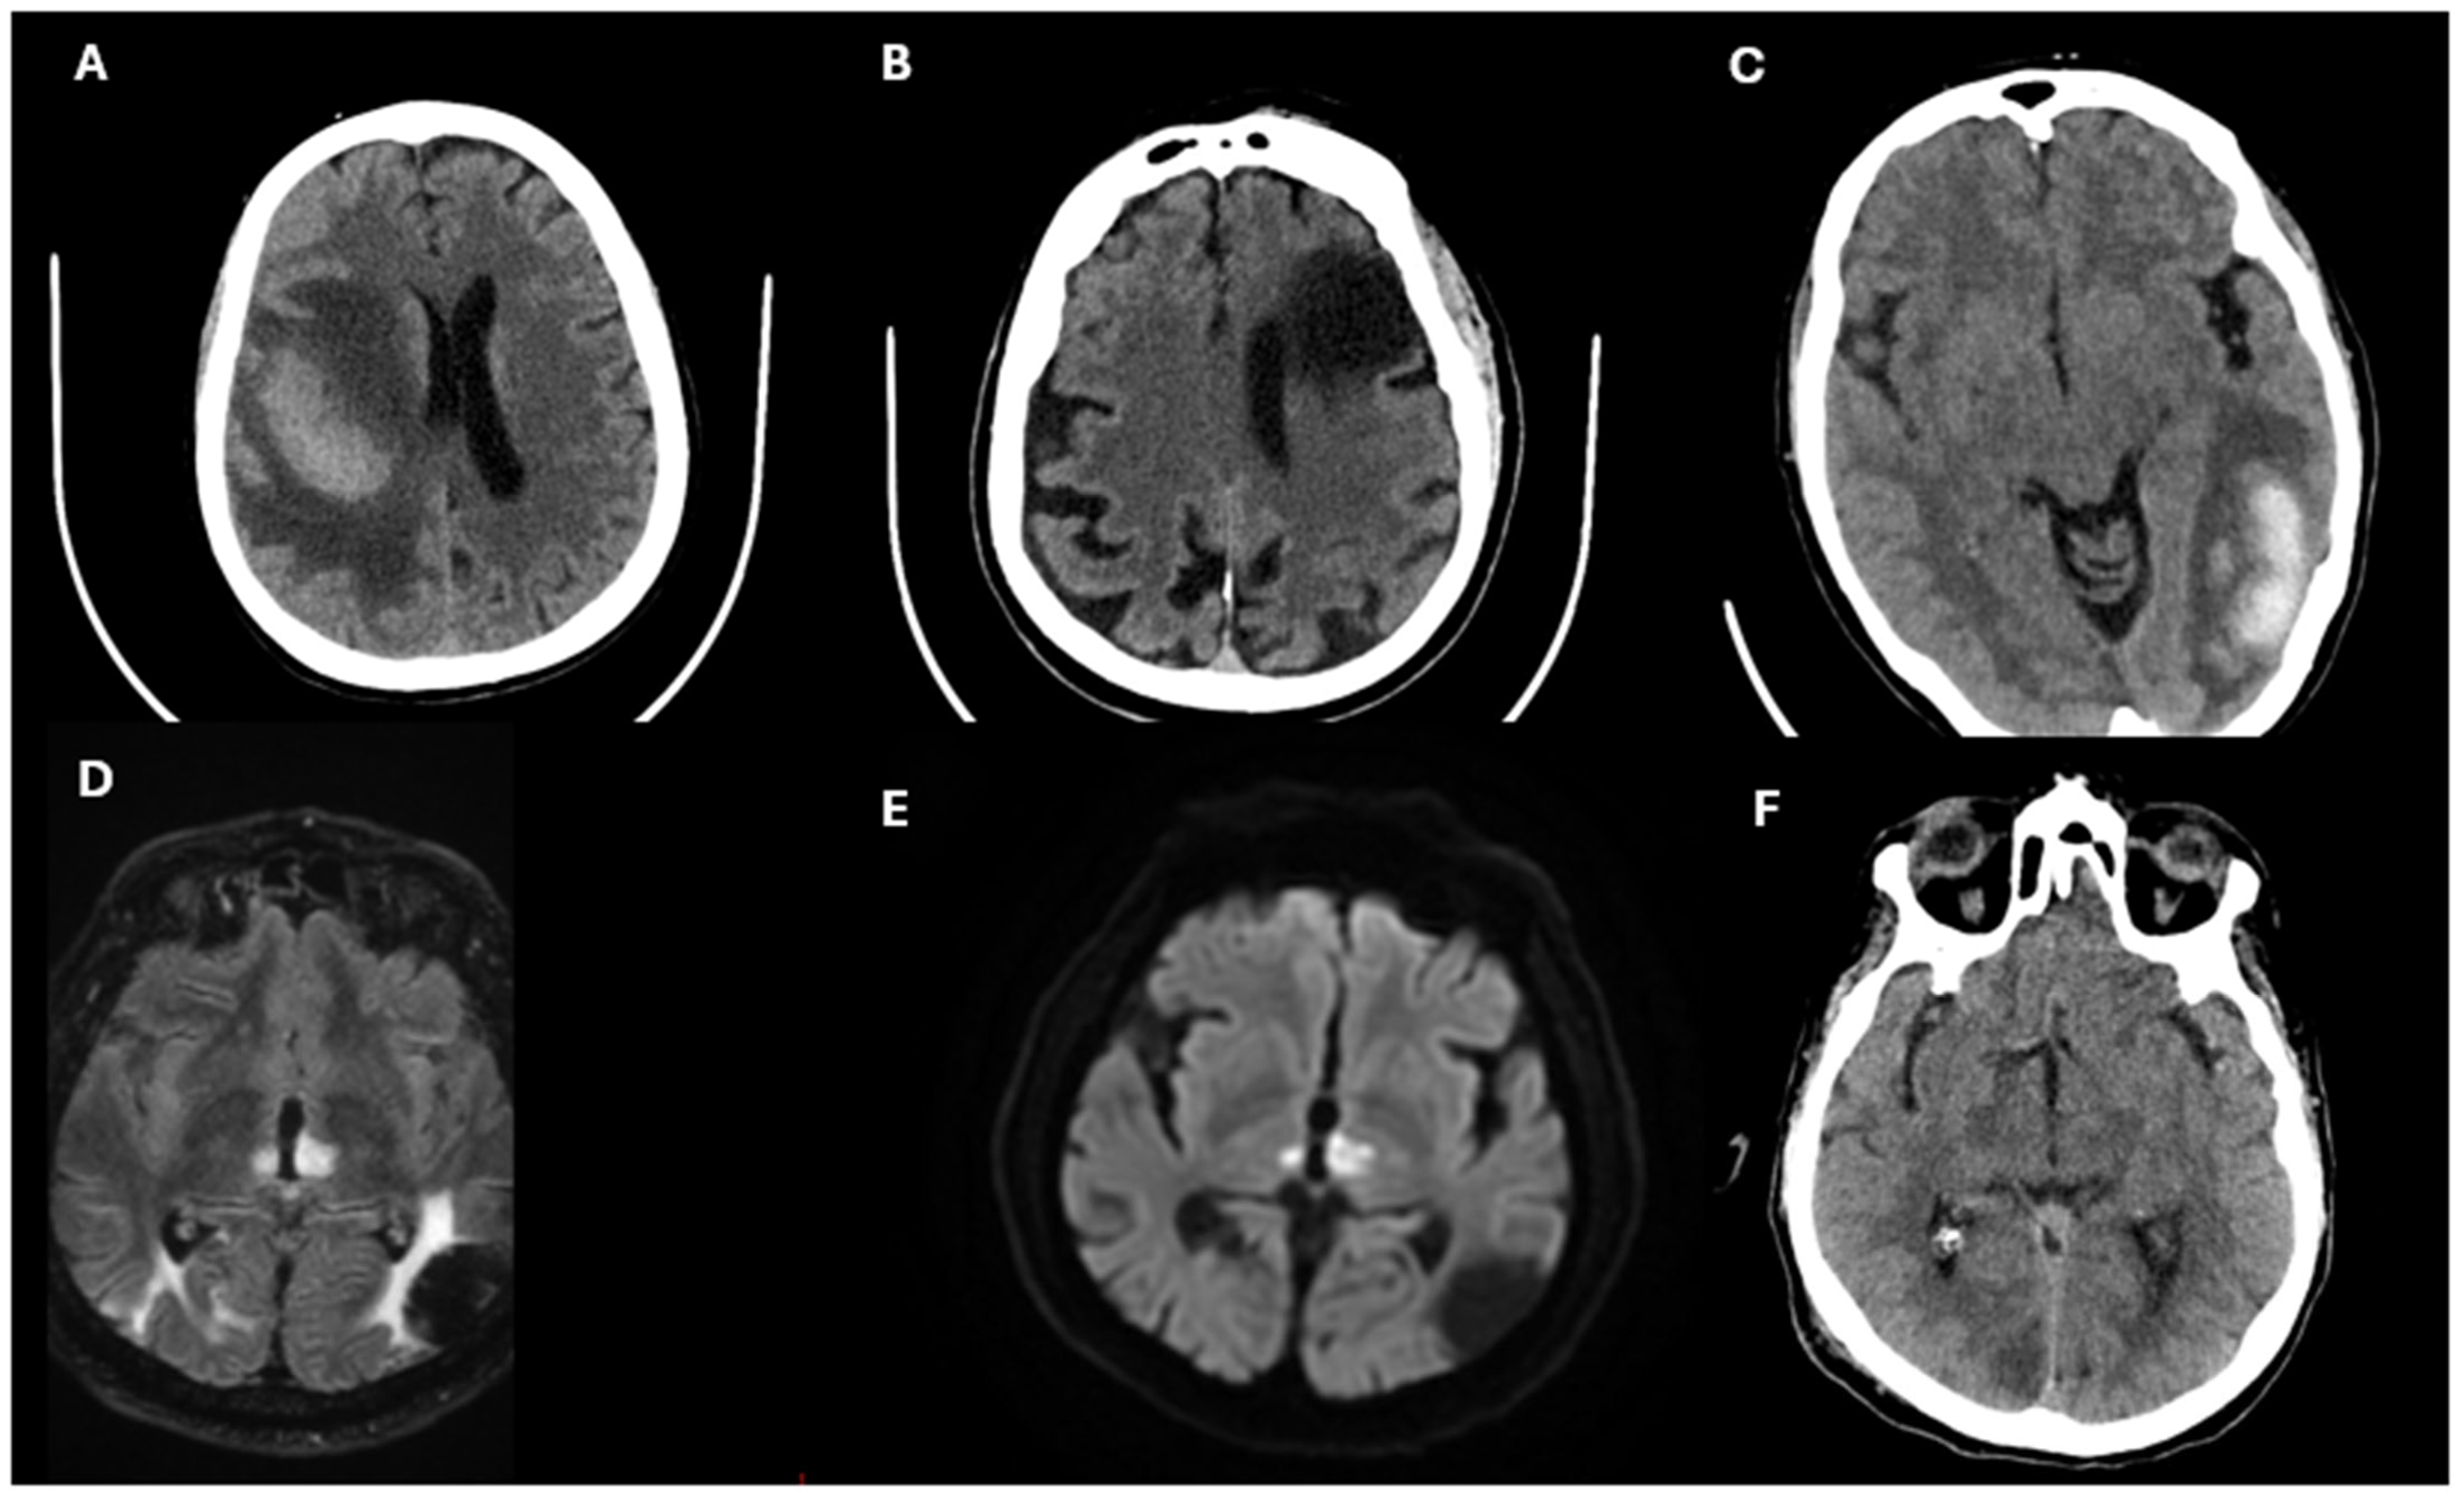

3.2. Diagnostic Approach in Stroke

3.3. Biomarkers in Stroke